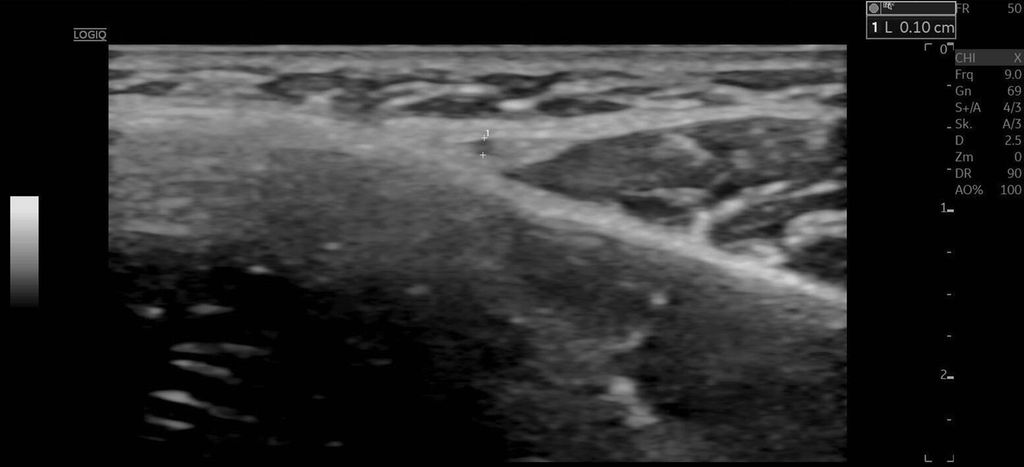

Die A. facialis imponierte beim Austritt im Bereich des Musculus masseter (oberhalb der Kieferlinie) vasospastisch mit einem maximalen Durchmesser von 1mm. Die abgeleitete systolische Spitzengeschwindigkeit betrug trotz der bestehenden Ischämie 20cm/s, ohne enddiastolische Komponente, was auf eine weitere periphere Vasokonstriktion hindeutete (Abb. 2 und 3).

Die A. facialis ist die Hauptarterie zur Blutversorgung des Gesichts und entspringt aus der A. carotis externa. Sie hat einen stark geschlängelten Verlauf und bildet zahlreiche Anastomosen mit benachbarten Arterien. Ihr Durchmesser variiert entlang ihres Verlaufs: Am Unterkieferrand liegt der mittlere Durchmesser bei 2,4mm, in der Wangenregion bei 1,9mm und im Bereich der Nasolabialfalte bei etwa 1,5mm. Die A. angularis, der Endast der A. facialis, weist einen Durchmesser von ca. 1,2mm auf. Die Flussgeschwindigkeit variiert je nach Region, beträgt aber durchschnittlich zwischen 20–50cm/s.1

Sonografisch lässt sich die A. facialis am besten an der Vorderseite des Musculus masseter detektieren. Sie zeigt eine deutliche Pulsation, und ihre Hauptäste – A. labialis inferior, A. labialis superior und A. angularis – sind aufgrund ihrer oberflächlichen Lage gut darstellbar.